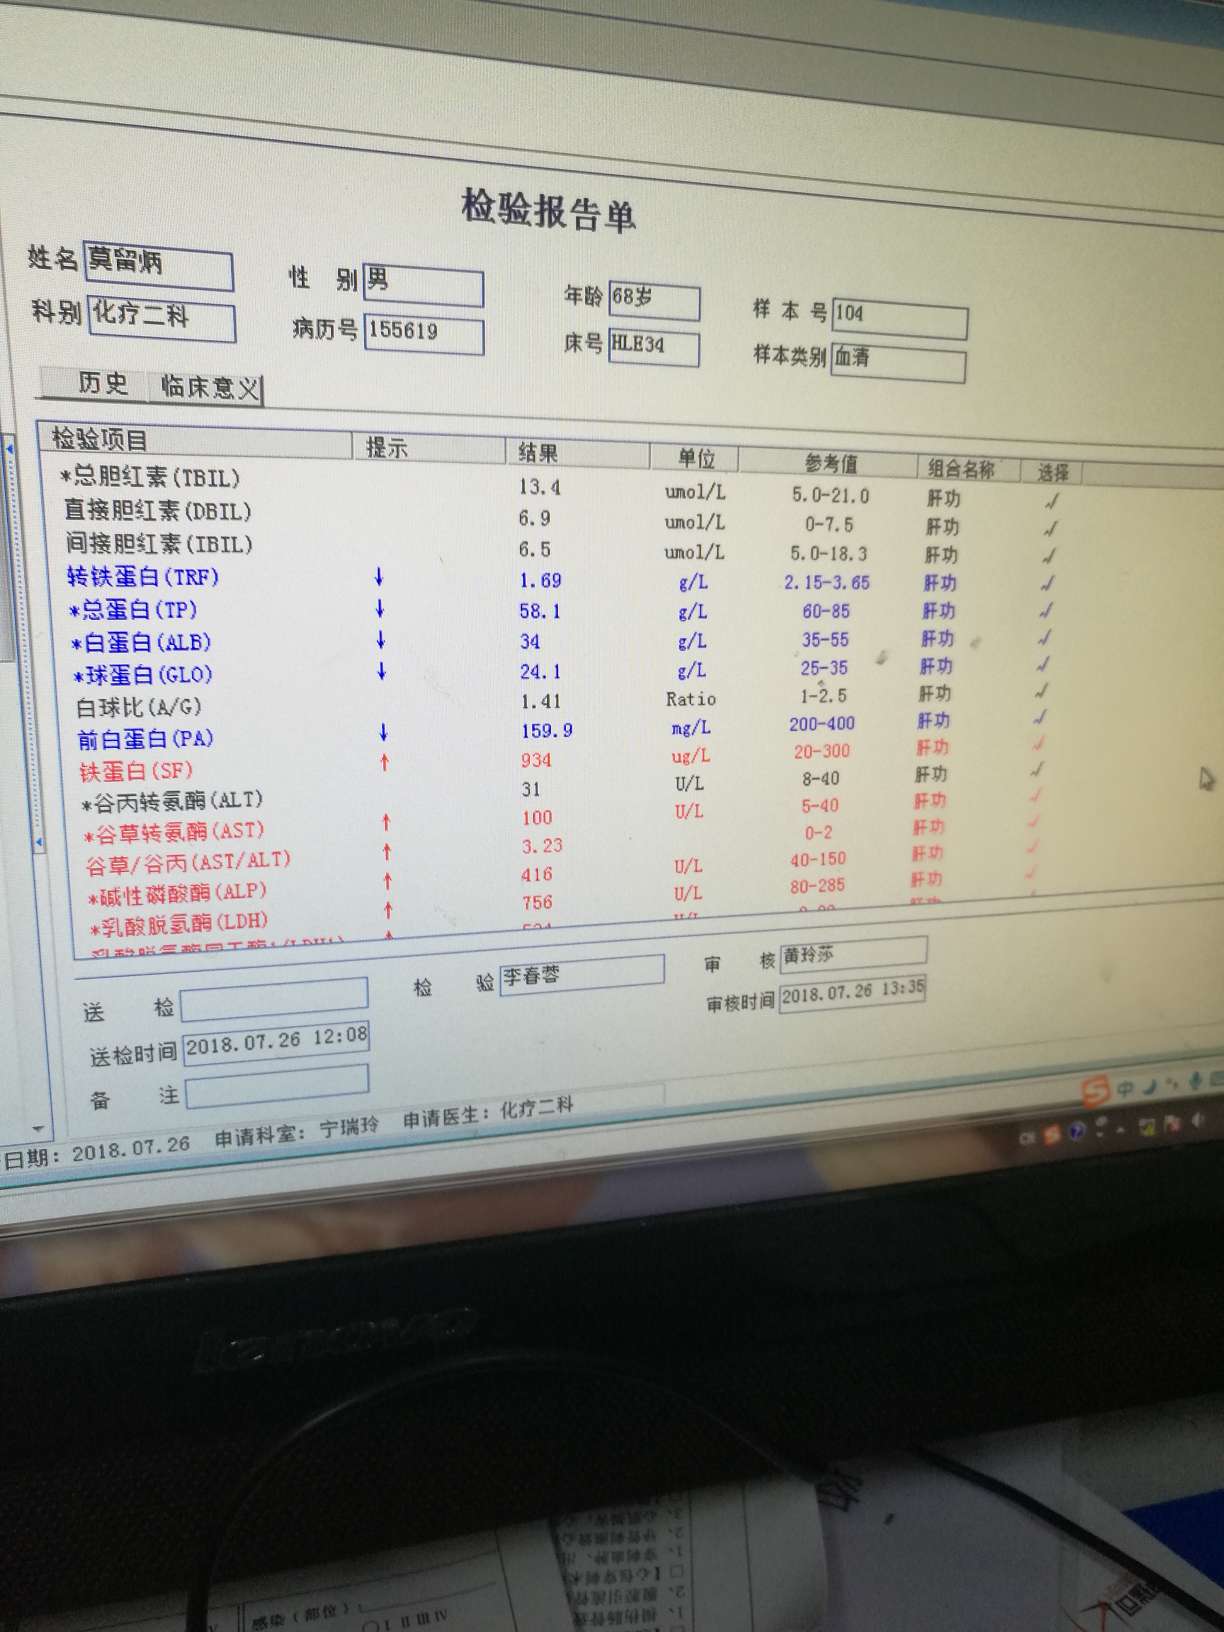

医生原来考虑用的治疗方案是美琣 卡鉑 恩度,但是现在考虑到我父亲的身体情况和肝损伤状况,决定化疗用美琣单药,3天后开始我父亲的第一次化疗。

想上免疫疗法,但是肝功能太差,需要把肝补好才能用K药。

肝部阴影多了很多,骨转,肾上腺都有,同时疑似有脑转,肿瘤标志物数值也升幅很大

肝部阴影多了很多,骨转,肾上腺都有,同时疑似有脑转,肿瘤标志物数值也升幅很大